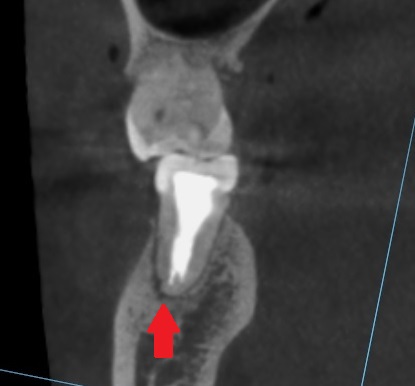

CTを別の方向から見ると、

根の先が黒くなっています。

ここですね。

細菌により膿がたまって、根の先の骨が溶けて黒く見えています。